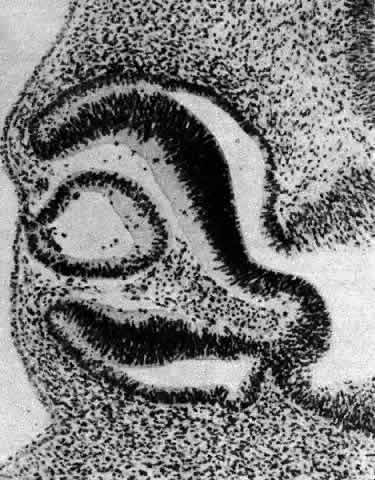

Other opacities that fall under the category of capsulolenticular cataracts are the polar cataracts. In this case, the opacities are situated at either pole of the lens and generally involve only the superficial cortical area. The relatively common anterior variety assumes a number of forms but is typically plaquelike and circumscribed. The size of the opacity may vary from a small dot to one that occupies the entire pupillary region. Because it may have a laminate appearance, it has also been called a pyramidal cataract. Similar opacities are observed in children who have had corneal ulcers during infancy. The fact that the fetal nucleus of the lens is not involved suggests an occurrence relatively late in intrauterine life. Occasionally, an opacity might be seen above the previously incurred derangement separated by an apparently normal lenticular zone, producing the so-called reduplicated cataract. In this case, it is believed that, following an initial disturbance, normal fibers are deposited, followed later by a new, sometimes more severe disturbance that produces a second region of opacification. There are a number of variations on this theme, and such opacities may assume myriad possible forms. It may be significant that these opacities are often associated with a strand or strands of pupillary membrane that bridge the iris (in the region of the collarette) to the polar cataract.181–183 Similar adhesions to the pupillary margin have been noted. Another observation has been that these cataracts are often associated with signs of keratitis, most notably corneal opacification. It is interesting that, histologically, the changes are similar to those observed in the adult human lens following corneal ulceration.177–180 The polar cataract is typically associated with a hyperplasia of the epithelium and a great deal of necrosis of lens fibers in the subepithelial area.184 Multistratification of the epithelium occurs as the cells fill a depression left by the necrotic fibers (Figs. 36 AND 37). The cells become spindle-shaped and produce PAS-positive material. Contrary to a long-held but erroneous notion, the plaque thus formed does not represent a metaplastic transformation of epithelial cells into fibroblasts.185 The plaque is often undermined by normal cuboidal epithelial cells and is eventually surrounded by capsulelike material (see Figs. 36 AND 37). The most reasonable explanation of the basis of this anomaly is the development of intrauterine inflammation. Although it has been suggested that the anterior polar cataract may be the result of a persistent vascular tunic that interferes with nutrition, the counterpart, the posterior polar cataract, need not be associated with hyaloid remnants, yet the histologic picture is quite similar.